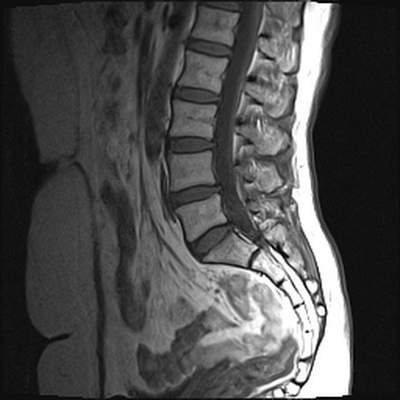

Снимок МРТ поясничного отдела позвоночника в сагиттальной проекции при остеохондрозе

МРТ позвоночника. Сагиттальная Т2-взвешенная МРТ, срединный срез поясничного отдела. Показана нумерация позвонков, измерения позвоночного канала (черная линия). Т- дуральный мешок с ярким ликвором. L- желтая связка. Sacrum - крестец. D - межпозвоночный диск. Голубым выделен остистый отросток, желтым - тело позвонка, Голубые точки - ход корешков.